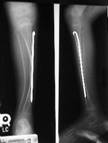

Radiografía de piernas afectadas por Osteogénesis ImperfectaNo existe, hoy en día, tratamiento curativo de la enfermedad.

El tratamiento actual más novedoso consta de dos fases, una farmacológica y otra quirúrgica. En la primera se administra pamidronato (Aredia®) por vía intravenosa cada dos o cuatro meses. Al mismo tiempo hay que hacer ejercicio, y tomar calcio en las dosis adecuadas.

El hueso es un órgano dinámico que se destruye y construye constantemente. Este fármaco lo que hace es retardar la destrucción y favorecer la construcción del hueso, con lo cual se produce un aumento de la densidad del hueso. De ese modo, se logra más calcio dentro del hueso, es más fuerte y tiene menos posibilidades de fractura. Ser constante en el tratamiento es difícil, tanto para el paciente como para su familia, porque se les administra durante tres horas varios días seguidos.

En cuanto a la parte quirúrgica, esta se basa en introducir un clavo dentro del hueso. Si está recto es más difícil que se quiebre. Los hay que acompañan el crecimiento del niño y también los que son completos, para adultos que ya no crecen y que son más fáciles de colocar (Rodding).

Como hemos comentado, existe un procedimiento quirúrgico llamado "rodding", que se utiliza con frecuencia en estos pacientes. Consiste en insertar barras metálicas en los huesos largos del cuerpo para reforzarlos y prevenir y/o corregir las deformidades. Esta cirugía suele restringirse a niños con enfermedad de moderada a severa y cuando tiene fracturas repetidas de uno o más huesos largos del cuerpo.